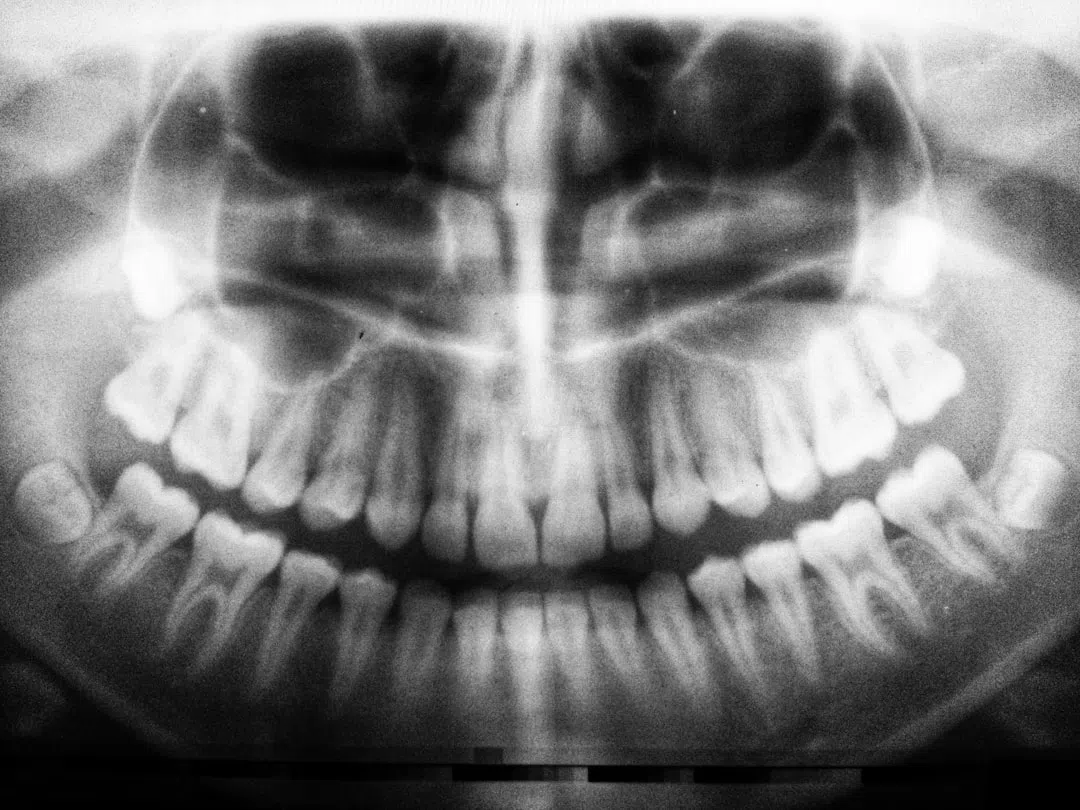

시술 전 상담에서는 치과 전문의와 충분히 이야기를 나누었고, 각 단계마다 세세한 설명과 함께 나의 치아 구조에 맞춘 맞춤 진료 계획이 제공되었습니다. 무엇보다도 치과의 청결함, 시술 도구의 위생 상태, 그리고 스텝들의 친절함이 큰 안심을 주었습니다.